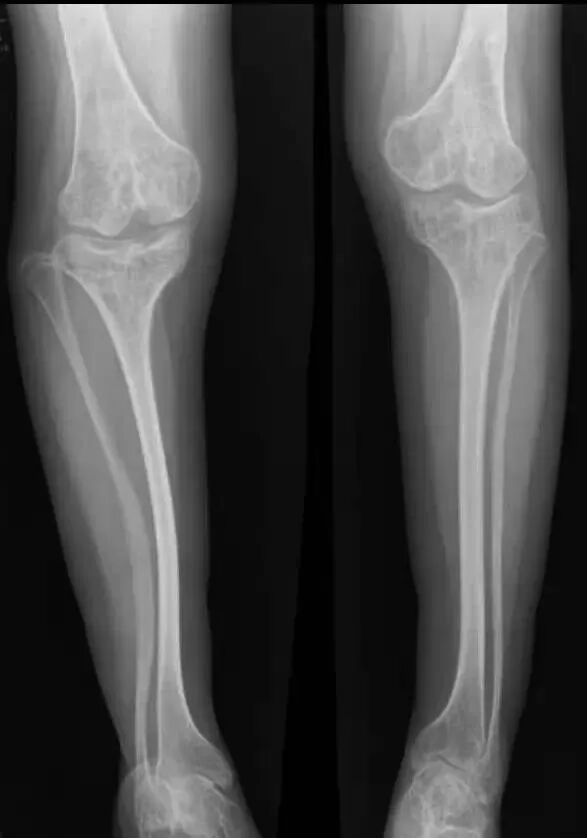

OI标志性特征是骨质脆弱反复骨折, 典型骨骼X线表现(见图二);成骨不全症的临床表现不仅限于骨骼,还常常累及其他结缔组织如眼、耳、皮肤、牙齿等(见图三)。根据临床表型, 澳洲悉尼大学的Sillence教授将OI 分成至Ⅰ-Ⅳ型[7]: Ⅰ型病情最轻, 最常见; Ⅱ最重, 通常围产期致死; Ⅲ型是存活者中最严重的, 常常身材矮小, 呈进行性骨骼畸形; Ⅳ型严重度介于Ⅰ型与Ⅲ型之间。近期发现的Ⅴ型OI 具有肥厚性骨痂、桡骨头脱位、前臂骨间膜钙化、桡骨干骺端下密集骺线等独特临床表现(见图四)。

图二:成骨不全症典型的X线表现

a.股骨干侧位片显示双侧非对称的股骨前弓弯曲愈合中的骨折(实心箭头)和已经愈合的骨折(空心箭头)

b. 胫骨侧位片显示双侧胫骨向前弯曲以及骨折愈合的不同阶段:早期愈合(实心箭头),进行性愈合中(空心箭头),已经愈合(三角);双侧胫骨呈现铅笔样畸形,尤其是腓骨及蜂巢状髓腔,特别是胫骨远端。

c. 骨盆平片显示严重的股骨近端髋内翻畸形以及基本完全愈合的转子下骨折;骨折愈合一般从内侧(压应力侧)开始,而骨折不愈合通常发生外侧表面(张应力侧);

d. 胸腰段脊柱侧位片显示椎体及附件广泛骨质疏松,椎体呈双凹征(空心箭头),扁平椎(实心箭头)以及各种程度的椎体前方楔形变,总的来说成骨不全患者脊柱骨骼改变与生长激素替代治疗的骨骼改变表现非常类似,骨硬化与骨吸收相互交错;

e. 肱骨的前后位片可以看到多条横形的硬化带,代表的是双磷酸盐治疗周期;同时还可以看到向外拉长、变薄变细的锁骨和肋骨以及增宽的肋间隙;

g.皮肤松弛症的X线片表现有时与成骨不全的比较类似,股骨干前后位片显示已经愈合的股骨干骨折;

h.上肢的前后位片显示双侧的尺骨向外侧弯曲成角,肱骨远端向内侧成角(实心箭头),同时伴有桡骨小头脱位(空心箭头)。